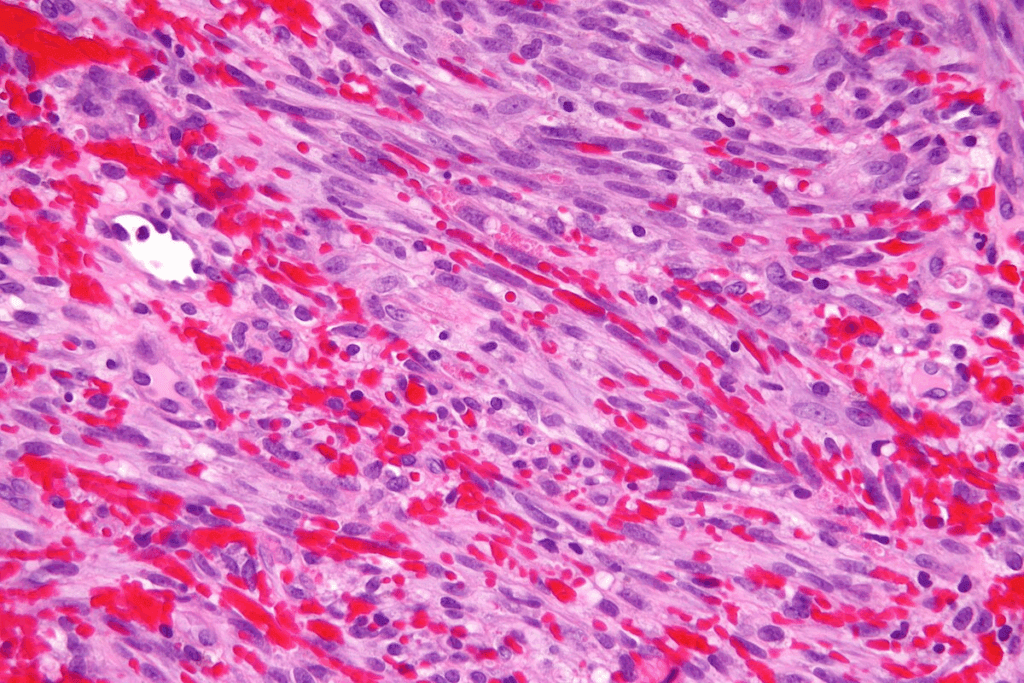

Histological Characteristics

The microscopic features of SCC include squamous cells with keratinization and intercellular bridges. These tumors are often high-grade and invasive. Accurate microscopic diagnosis is key to telling SCC apart from other bladder cancers.

By grasping the definition, classification, and microscopic features of SCC, we can better understand its uniqueness and the challenges it brings to diagnosis and treatment.